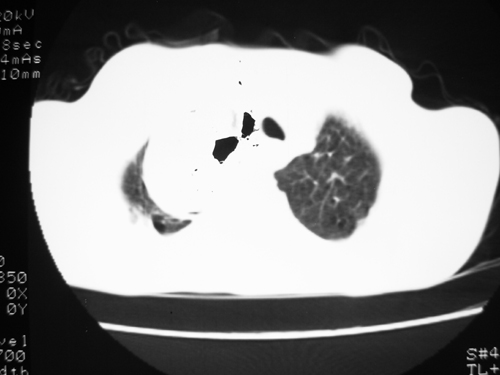

以下是引用yangyudong333在2008-4-29 5:46:00的发言:[br]1左上叶结节呈分叶状,边缘毛刺,考虑肺癌并纵隔淋巴结转移可能性大,结核待排,[br] [br]2右侧多发包裹性胸腔积液

以下是引用zsl6918在2008-4-29 9:15:00的发言:[br]右侧包裹性积液穿刺术后改变,肺内多发结节不除外转移可能。建议查胸水,问病史。